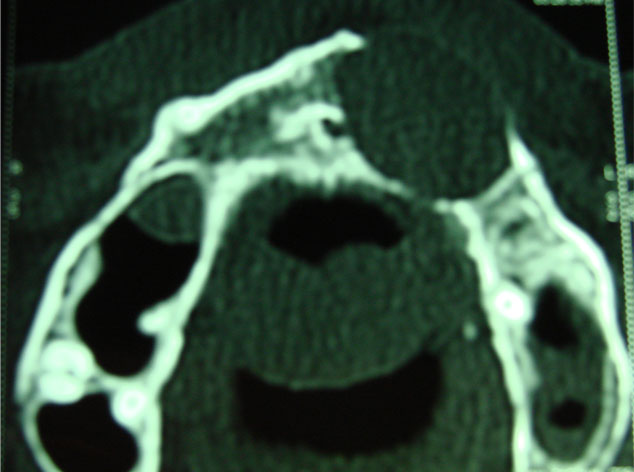

Aunque su estirpe anatomopatológica sea benigna, son quistes que en algunos pacientes provocan grandes destrucciones maxilares, porque crecen de forma asintomática durante años.